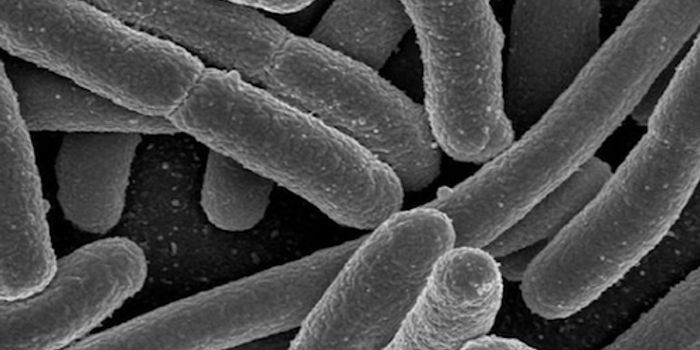

MAR 19, 2017MicrobiologyIt can be incredibly challenging to give a patient the proper treatment when they are infected by an antibiotic-resistan ...

JAN 11, 2017CancerSalmonella, the bacteria that is bane of all restaurants and grocery stores, has now been transformed into “tumor- ...

OCT 18, 2019Health & MedicineMultidrug-resistant bacteria are frequently found in hospitals and long-term nursing facilities causing one of the large ...

AUG 23, 2022MicrobiologyWith effort, we all can help counter the rise of bacterial pathogens that resist the effects of multiple antibiotics.